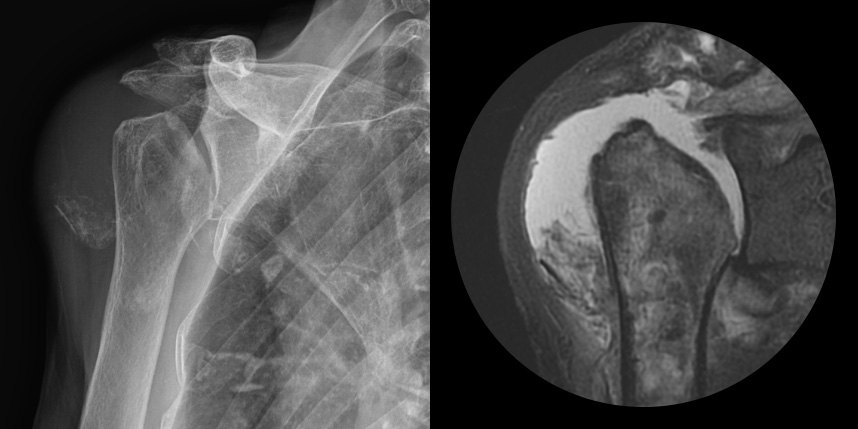

어깨 퇴행성은 많이 써서 닳고 노화에 따른 변화가 생긴 것으로, 말 그대로 어깨가 많이 사용되면서 연골이 닳아서

마모돼어 생기는 관절염입니다. 어깨 회전근개 관절병증 원인으로는 어깨 힘줄 파열을 방치했을 때 관절이 틀어진 상태에서 계속

사용하게 되면 관절이 많이 상해서 관절염까지 진행되며, 이런 경우 회전근개파열의 결과로 생긴 관절병이라고 합니다.

최근에 퇴행성 관절염, 류마티스 관절염 이외에도 많은 환자가 발생하고 있습니다.